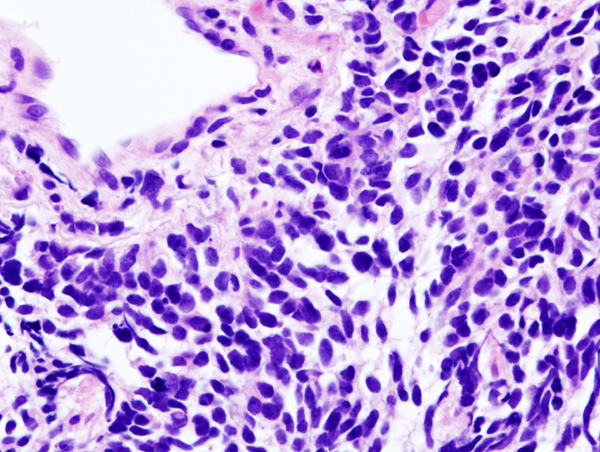

Bildgebung

© wikipedia.org/Lange123, CC BY-SA 3.0